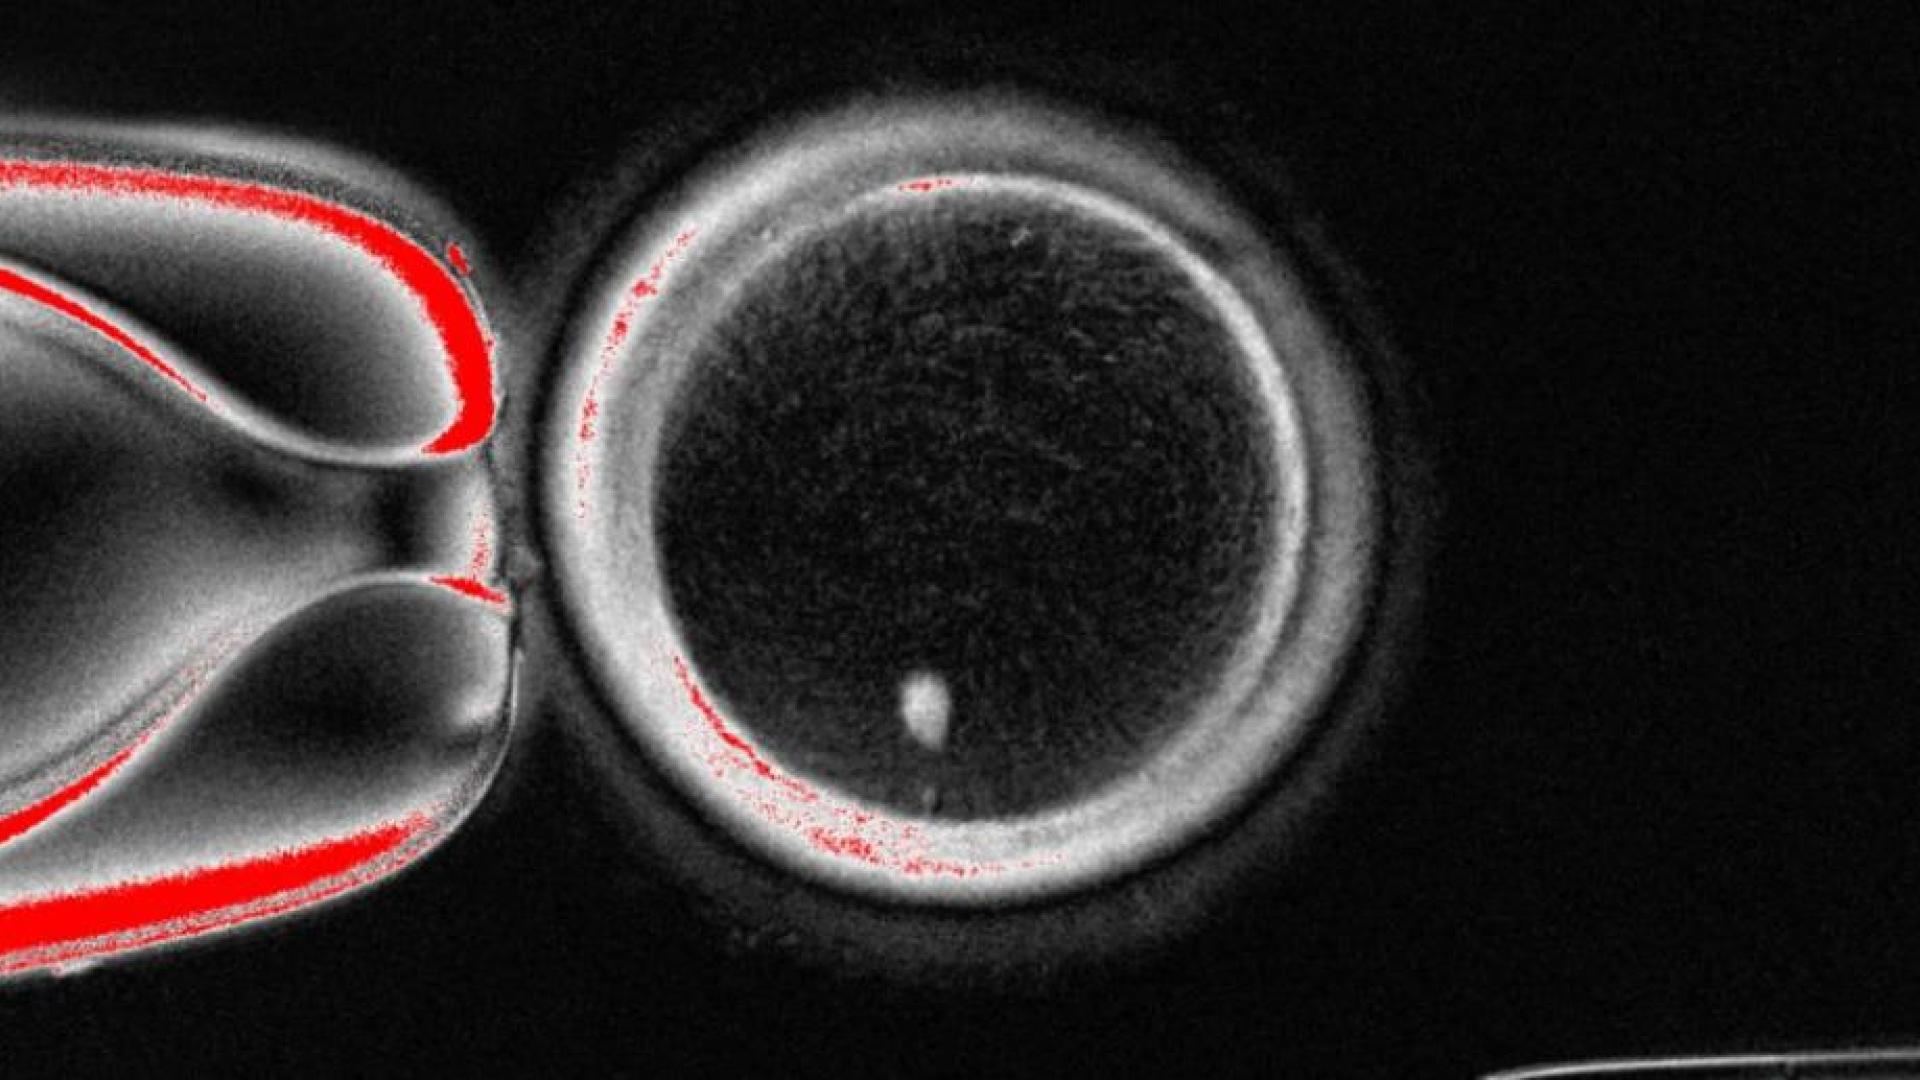

El equipo extrajo el núcleo de las células somáticas de la piel y lo insertó en ovocitos de donantes a los que se les había extraído el núcleo.

Para resolver el problema del conjunto extra de cromosomas indujeron un proceso que denominaron "mitomeiosis", que imita la división celular natural y provoca que se descarte un conjunto de cromosomas, dejando un gameto funcional.

Aunque la segregación cromosómica se produjo de forma aleatoria, se conservaron una media de 23 cromosomas.

Los investigadores fertilizaron en laboratorio 82 ovocitos funcionales generados, de los que solo un 9 % se llegó a desarrollar durante seis días, hasta las fase de blastocito, cuando se paró el experimento, lo que coincide con el momento en que normalmente se transferirían al útero en un tratamiento de fecundación in vitro.